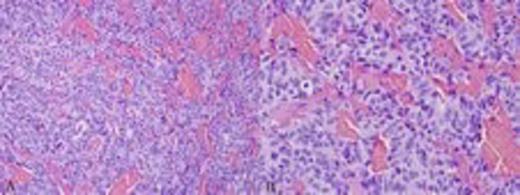

The patient underwent transsphenoidal resection of the pituitary mass to decompress his chiasm and obtain pathology. H&E staining demonstrated a neuroendocrine neoplasm (Fig. 2) with 4 mitotic figures per 10 high-power fields and no necrosis. The tumor appeared to be growing in the vicinity of the pituitary as evidenced by a small portion of Rathke’s cleft epithelium. Based on the morphologic appearance, the main differential included pituitary adenoma versus metastatic carcinoid tumor. Immunohistochemical stains (Fig. 3) showed tumor cells negative for prolactin, adrenocorticotropic hormone, human growth hormone, luteinizing hormone, follicle-stimulating hormone, and thyroid-stimulating hormone. Based on these results, the tumor was diagnosed as a metastatic carcinoid tumor originating from lung primary.

Fig. 3: Immunohistochemical stains confirmed the neuroendocrine nature of the tumor, with positive staining for synaptophysin (a) and CD56 (b). The tumor demonstrated TTF-1 nuclear expression (c) and S100-positive sustentacular cells (d), which are typical features of a pulmonary carcinoid tumor. All images are at 200X magnification

The key diagnostic features in this case include a trabecular growth pattern, sustentacular cells surrounding nests of tumor cells, neuroendocrine features with copious cytoplasm, and nuclear expression of TTF-1. Although pituitary adenomas can have somewhat similar morphologic features, the presence of strong and diffuse TTF-1 nuclear expression with negative staining for pituitary hormones excludes the diagnosis of a pituitary adenoma. Given the patient’s history of primary small cell carcinoma of the lung, metastatic small cell carcinoma was also considered. The distinction between carcinoid tumor and small cell carcinoma is based exclusively on the morphologic features of the tumor. In contrast to carcinoid tumors, small cell carcinomas have high-grade features, including tumor cells with scant cytoplasm, nuclear molding, brisk mitotic activity, apoptotic cell death, and extensive necrosis, none of which were seen here.